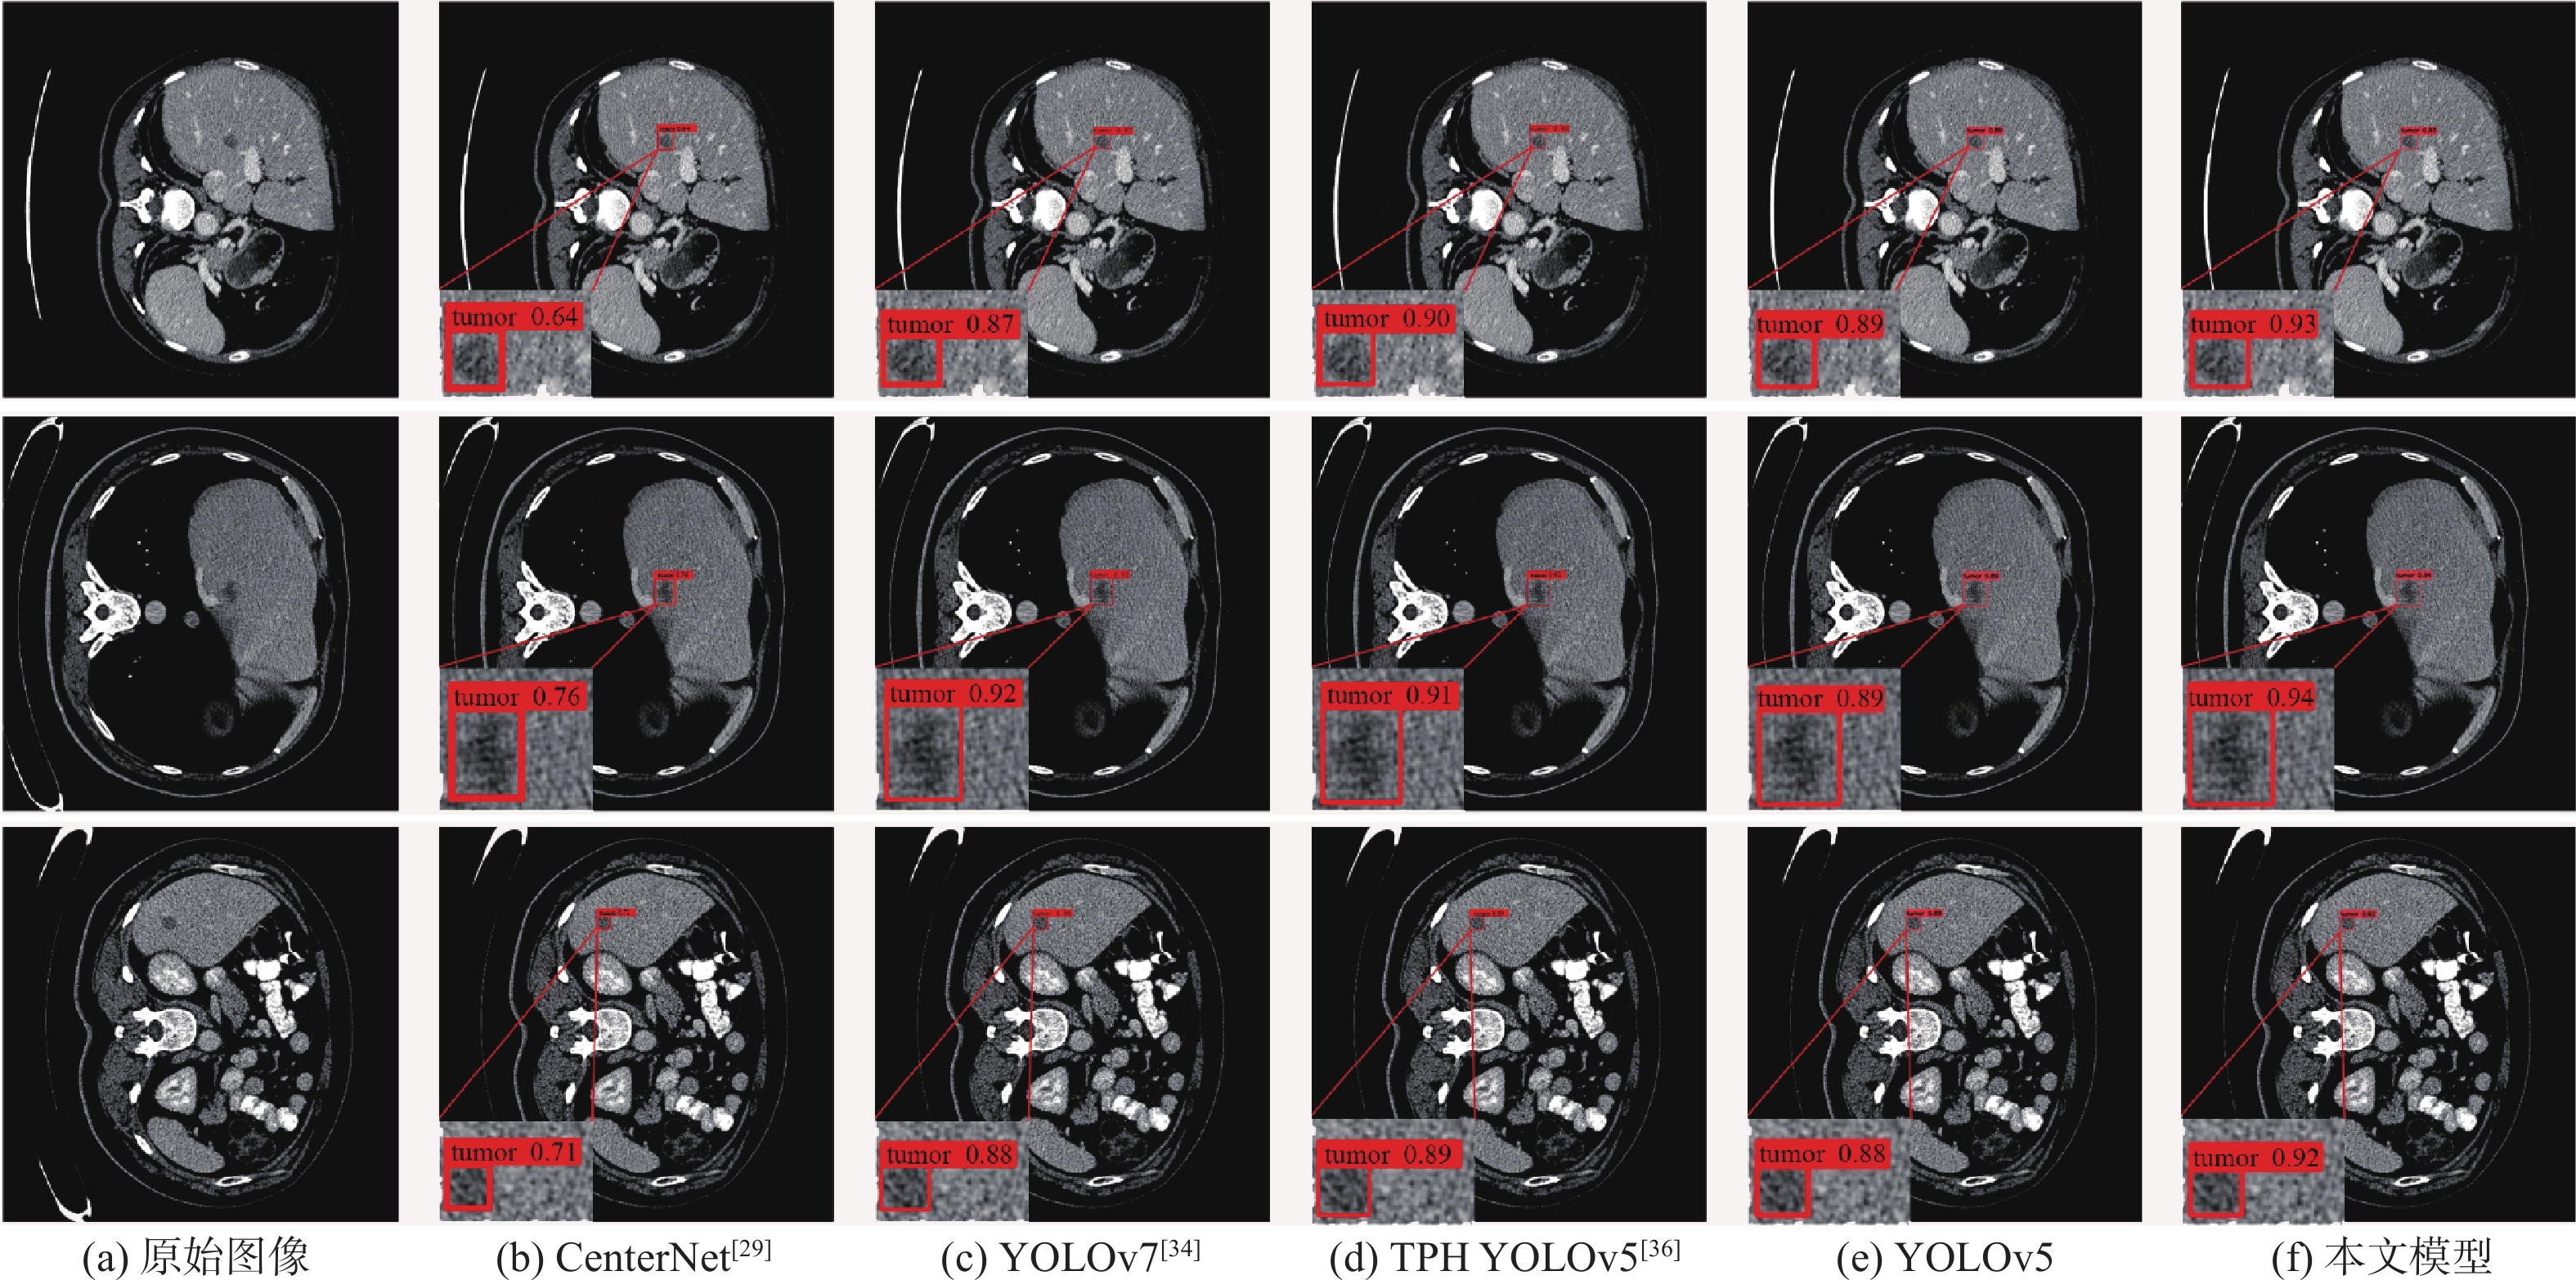

A low-dose CT deep unfolding network based on a sparse transform priors constrain

WANG Yue, ZHANG Xiong, SHANGGUAN Hong, CUI Xueying, ZHANG Pengcheng, GUI Zhiguo

2026, 52(4): 1199-1210. doi: 10.13700/j.bh.1001-5965.2024.0049

Abstract:

Deep iterative unfolding networks have garnered a lot of attention lately because of their great learning capabilities and good interpretability. The regularization terms in existing CT image reconstruction methods mostly focus on information within a specific domain, leading to issues such as edge blurring and information loss in the reconstructed results. Therefore, a sparse transform prior constrain based deep unfolding network is proposed for sparse-view CT reconstruction. Two regularization terms with complementary information—transform-domain sparse regularization and pixel-domain consistency regularization—are created in consideration of the important roles that both pixel-domain and transform-domain information play in picture reconstruction. Based on these, the objective function for sparse-view CT reconstruction is redesigned. Furthermore, a new deep unfolding network for iterative reconstruction of low-dose CT is created by mapping a set of constraint relationships established from an iterative optimization solution for the constructed objective function. Experimental results demonstrate that the algorithm presented in this paper achieves a great improvement on average peak signal to noise ratio (PSNR) and visual information fidelity (VIF) compared to the classical FISTA algorithms.